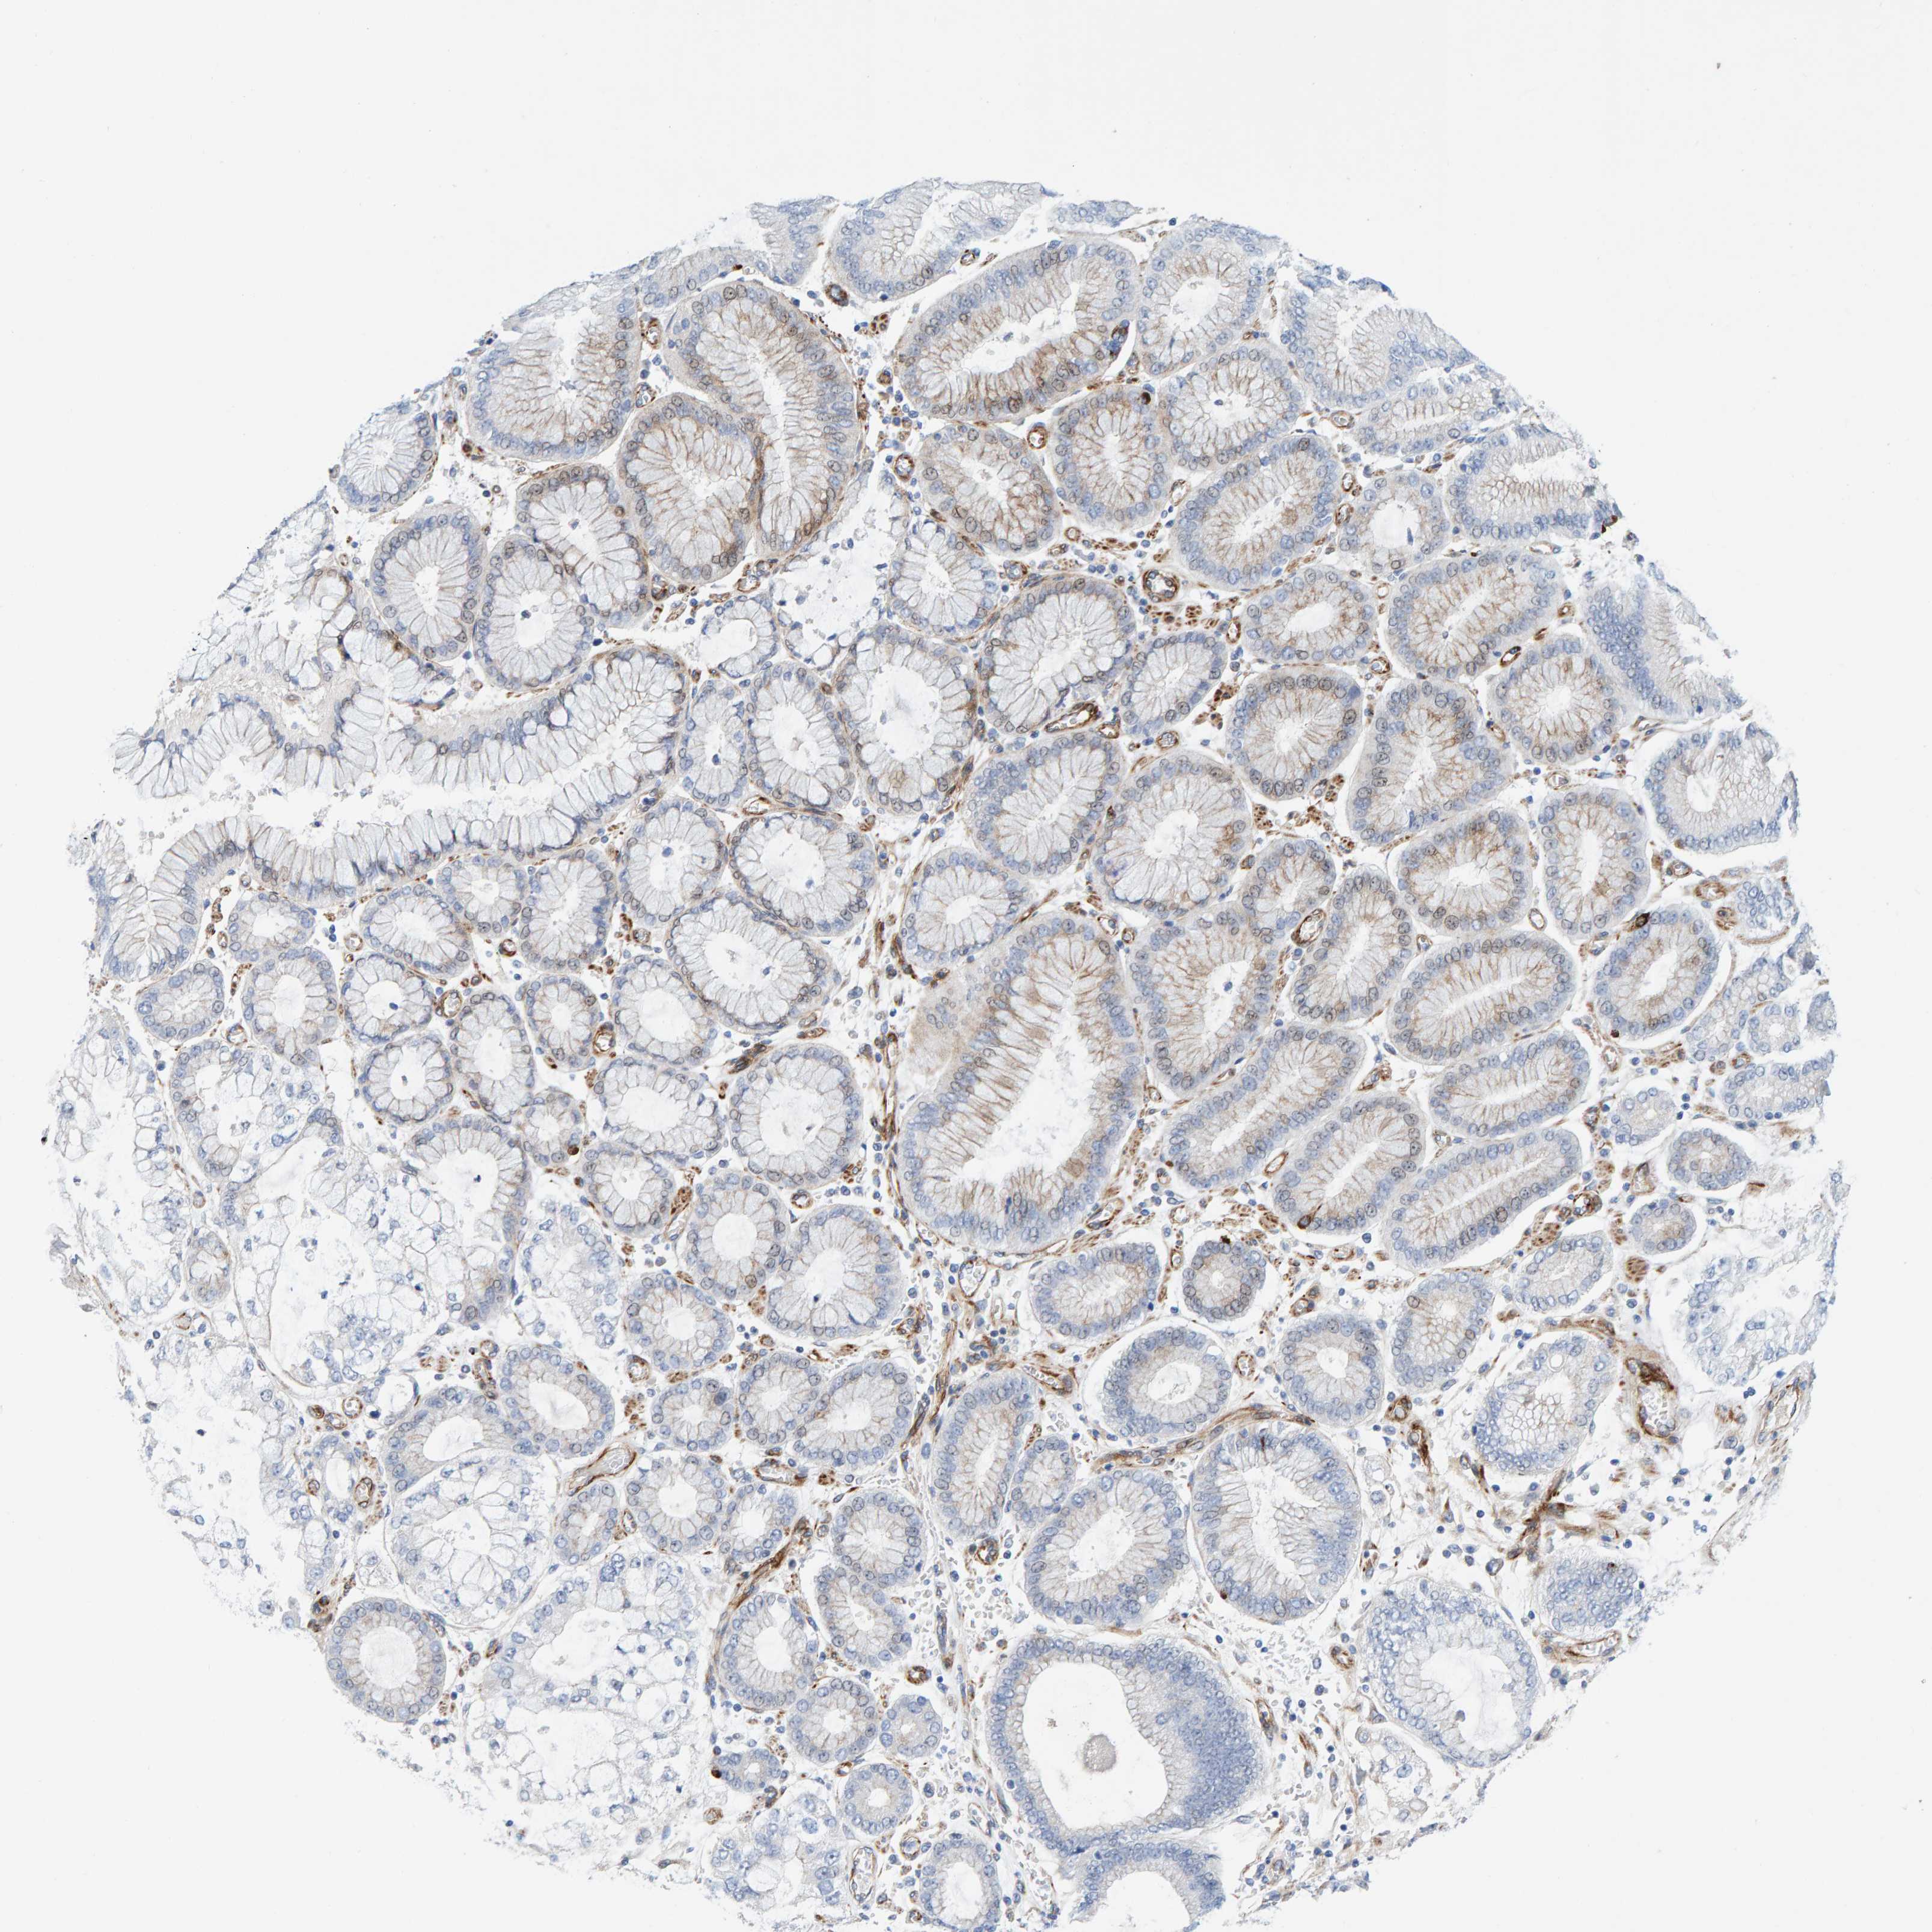

STOMACH CANCER - Protein expressioni

A mouse-over function shows sample information and annotation data. Click on an image to view it in a full screen mode. Samples can be filtered based on level of antibody staining by selecting one or several of the following categories: high, medium, low and not detected. The assay and annotation is described here.

Note that samples used for immunohistochemistry by the Human Protein Atlas do not correspond to samples in the TCGA dataset.

Antibody stainingi

Antibody staining in the annotated cell types in the current human tissue is reported as not detected, low, medium, or high, based on conventional immunohistochemistry profiling in selected tissues. This score is based on the combination of the staining intensity and fraction of stained cells.

Each image is clickable and will lead to virtual microscopy that enables deeper exploration of all samples and also displays staining intensity scores, fraction scores and subcellular localization as well as patient and tissue information for each sample.

Antibody HPA023202

Antibody CAB017030

Staining

High

Medium

Low

Not detected

Intensity

Strong

Moderate

Weak

Negative

Quantity

>75%

75%-25%

<25%

None

Location

Nuclear

Cytoplasmic/membranous

Cytoplasmic/membranous,nuclear

Adenocarcinoma, NOS

Adenocarcinoma, High grade